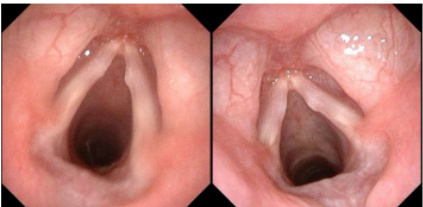

图3- 1 电子喉镜检查结果显示观察组休声后息肉体积较前期减小

图 3- 2 电子喉镜检查结果显示对照组训练后声带息肉体积较前期

减小

图3- 3 电子喉镜检查结果显示对照组较观察组声带闭合间隙更小